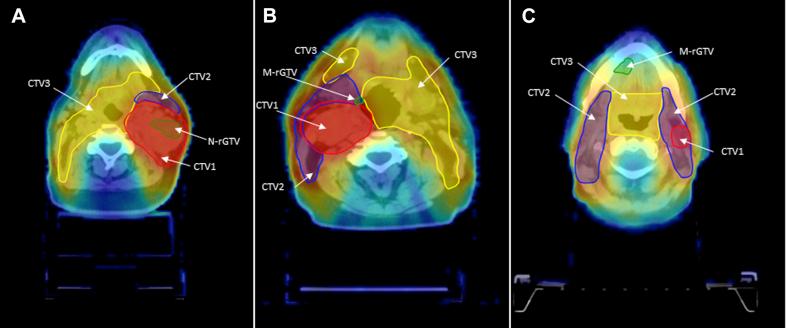

We reviewed the data of 260 patients who were irradiated between 2000 and 2015 and had a median follow-up time for surviving patients of 61 months. The mucosal and nodal recurrences were manually delineated on computed tomography images demonstrating the recurrences. The images were overlaid on the treatment plan using deformable image registration. The locations of the recurrences were determined relative to the original planning target volumes and doses using centroid-based approaches. Subsequently, the pattern of failures were classified into 5 types based on combined spatial and dosimetric criteria: A (central high dose), B (peripheral high dose), C (central elective dose), D (peripheral elective dose), and E (extraneous dose). For patients with type A failure with simultaneous nontype A lesions, the overall pattern of failures was defined as type A.

Thirty-two patients had mucosal or nodal recurrences. The most common clinical nodal stage was N2b (66%). Preradiation therapy neck dissections were performed in 6 patients. The median dose delivered to clinical tumor volume 1 was 66 Gy. The majority (84%) had total/partial pharyngeal mucosa elective irradiation. Twenty-three patients had nodal recurrences, 8 had mucosal recurrences, and 1 had both nodal and mucosal recurrences. Twenty-one patients (91%) had type A nodal failure, and 7 of the mucosal failures (89%) were type C.